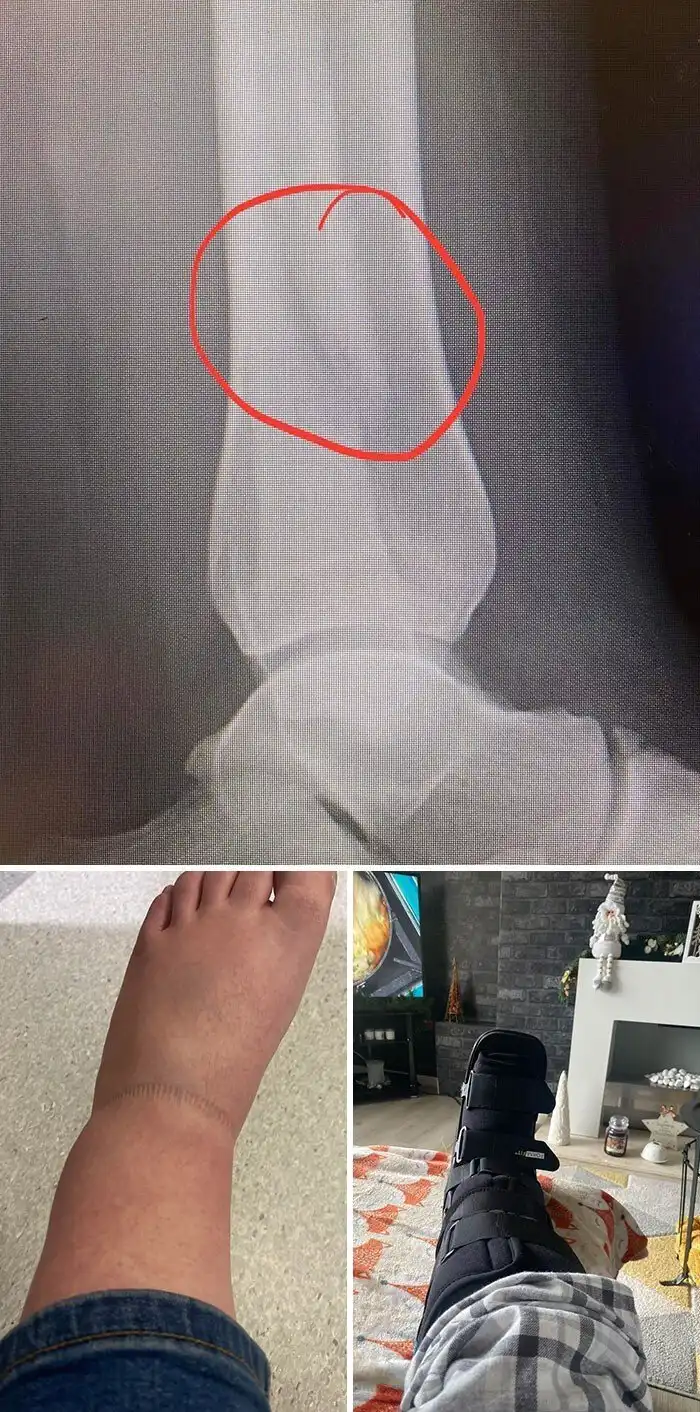

21. "Я сломал малоберцовую кость через 2 часа после того, как похвастался перед семьей, что никогда раньше не ломал кости. На Рождество"